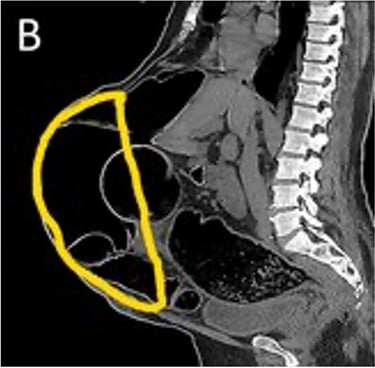

Realizamos una Tomografía Axial Computarizada con reconstrucción en 3D de la Pared Abdominal y de la hernia, cuando corroboramos que todo está listo, el siguiente paso es elegir el tipo de malla quirúrgica a colocar en la cirugía.